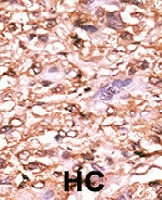

Formalin-fixed and paraffin-embedded human hepatocellular carcinoma tissue reacted with TP53 (phospho T18) polyclonal antibody (Cat # PAB0568) which was peroxidase-conjugated to the secondary antibody followed by AEC staining. This data demonstrates the use of this antibody for immunohistochemistry; clinical relevance has not been evaluated. HC = hepatocarcinoma.